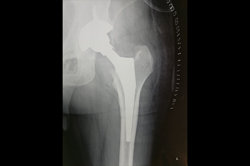

Total Hip Replacement - THR